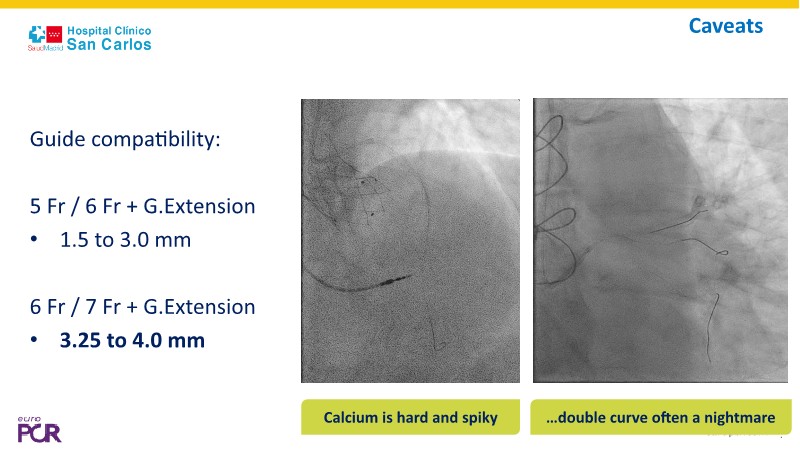

Discover how the next-generation RevoEdge high-pressure cutting balloon is transforming PCI with innovative design and proven clinical outcomes. This session presents a multicenter randomised trial and real-world case discussions, showcasing RevoEdge’s effectiveness in tackling resistant, complex lesions—including long, tortuous, and fibrotic cases. Learn practical tips, tricks, and intravascular imaging insights to optimize lesion preparation and improve patient outcomes. Don’t miss this opportunity to see how RevoEdge helps you cut through challenges and conquer PCI complexities.

- To explore the innovative design of RevoEdge: the next-generation high pressure cutting balloon

- To learn about the clinical benefits and tips and tricks of using RevoEdge high pressure cutting balloon in different types of complex lesions through case-based discussion